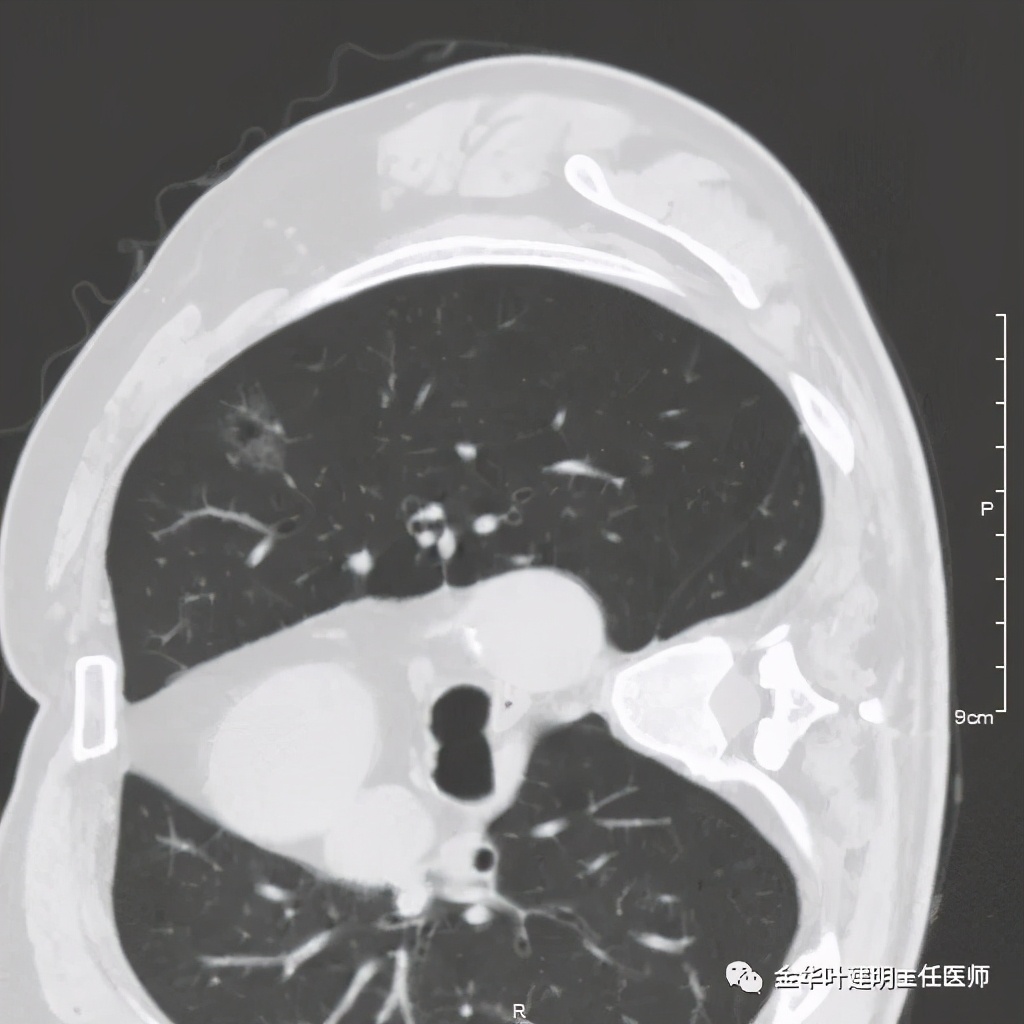

六、神经内分泌癌(此例为不典型类癌,小细胞癌以后再总结):

影像特征:不典型类癌一般圆形生长,实性,边缘比较光滑,但硬度不够。侵蚀力也不够。就像这例,我们发现其与肺动脉接触的地方,居然无法推压血管,反而肿瘤被血管占据了其生长的位置,在支气管内,肿瘤也是对支气管壁没有造成明显的破坏。也就是说 圆形边清较软、侵蚀力弱的实性结节 要考虑类癌的可能性。